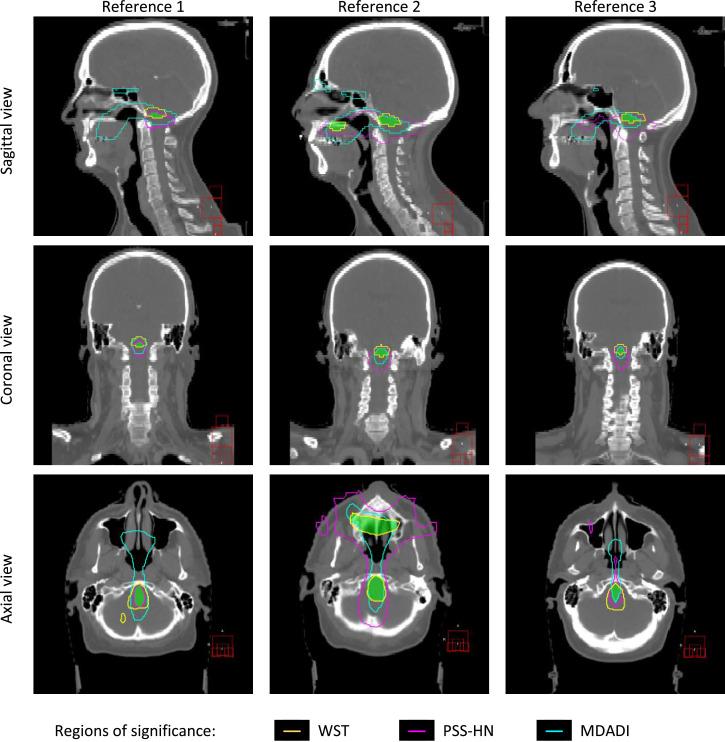

We used data from 104 patients with oropharyngeal cancer treated with definitive (chemo)radiation therapy. Swallow function was assessed pretreatment and 1 year posttreatment using 3 validated measures: MD Anderson Dysphagia Inventory (MDADI), performance status scale for normalcy of diet (PSS-HN), and water swallowing test (WST). For IBDM, we spatially normalized all patients' planning dose matrices to 3 reference anatomies. Regions where the dose was associated with dysphagia measures at 1 year were found by performing voxel-wise statistics and permutation testing. Clinical factors, treatment variables, and pretreatment measures were used in multivariable analysis to predict each dysphagia measure at 1 year. Clinical baseline models were found using backward stepwise selection. Improvement in model discrimination after adding the mean dose to the identified region was quantified using the Akaike information criterion. We also compared the prediction performance of the identified region with a well-established association: mean doses to the pharyngeal constrictor muscles.

IBDM revealed highly significant associations between dose to distinct regions and the 3 outcomes. These regions overlapped around the inferior section of the brain stem. All clinical models were significantly improved by including mean dose to the overlap region (P ≤ .006). Including pharyngeal dosimetry significantly improved WST (P = .04) but not PSS-HN or MDADI (P ≥ .06).

In this hypothesis-generating study, we found that mean dose to the inferior section of the brain stem is strongly associated with dysphagia 1 year posttreatment. The identified region includes the swallowing centers in the medulla oblongata, providing a possible mechanistic explanation. Further work including validation in an independent cohort is required.